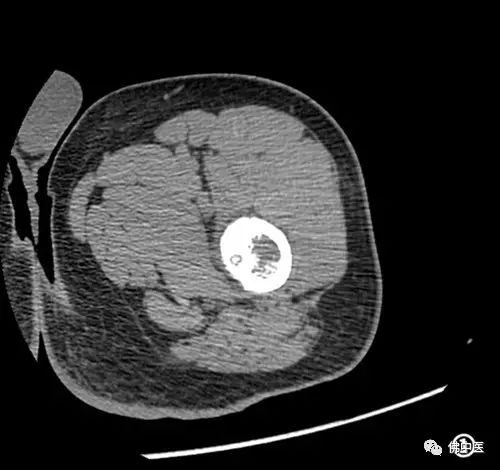

术前CT检查

为此,经骨病专科团队讨论,在麻醉科、医学影像科等的全程协助下,在院内首次创新性地采用CT引导下经皮穿刺射频消融术治疗骨样骨瘤。术后当晚患者疼痛症状消失,两天后康复出院。